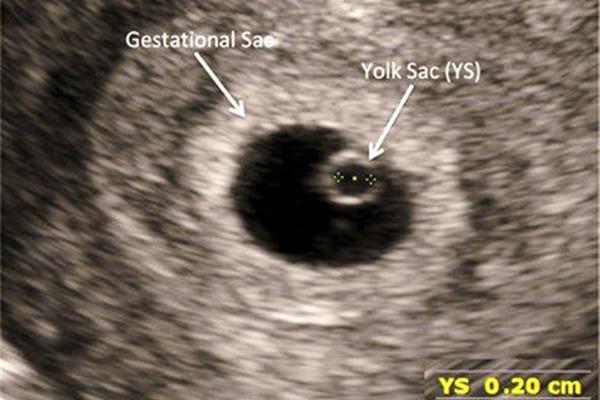

۱. ساک حاملگی

ساک حاملگی اولین ساختاری است که معمولاً در هفتههای ۴ و ۵ در رحم دیده میشود. حضور آن نشانهای اولیه از بارداری سالم است و فضایی را برای رشد جنین فراهم میکند.

۲. کیسه زرده (Yolk Sac)

در حدود هفتههای ۵ تا ۶، کیسه زرده درون ساک حاملگی دیده میشود. این کیسه نقش اصلی را در تغذیه اولیه جنین ایفا میکند تا زمانی که جفت بهطور کامل تشکیل شود. مشاهده کیسه زرده در سونوگرافی نشاندهندهی رشد طبیعی بارداری است.